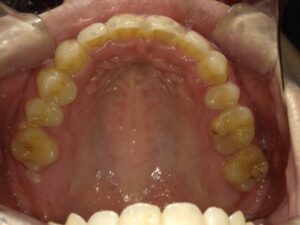

矯正治療が終了しました。

右上の抜いた大きな歯のスペースもしっかり閉じることができ、前歯も綺麗に並んでいると思います。

口元の印象も大きく変わったと、患者さんに喜んでいただけました。